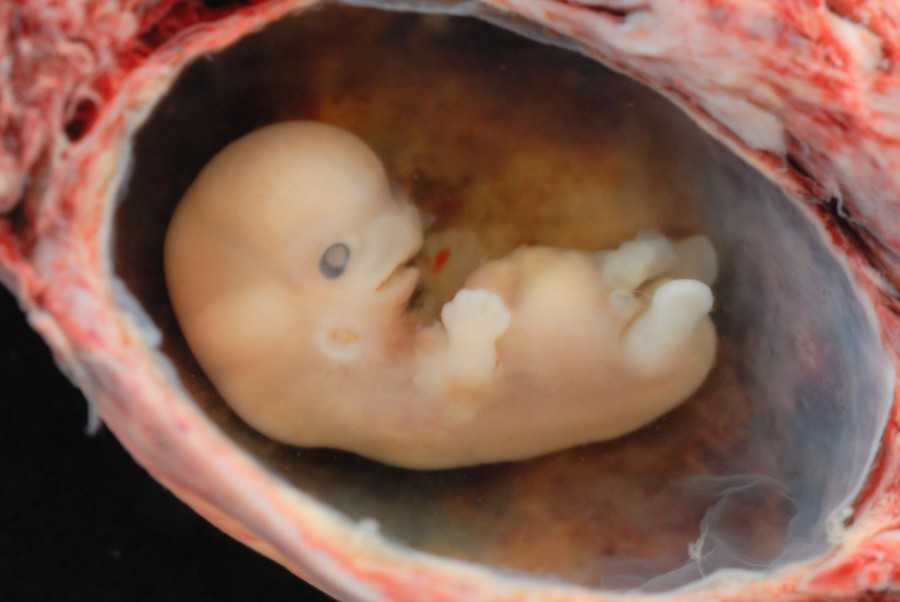

Вот так выглядит твой малыш на 9 неделе (фото плода)

Фото плода и живота матери на сроке 9 недель

Как выглядит эмбрион на 9 неделе? Ваш кроха еще подрос. У него уже начинает формироваться личико, удлиняются конечности, появляются пальчики. Именно на данном этапе ребенок прогрессирует и становится не эмбрионом, а плодом, поскольку большой палец на руке разворачивается так, что прижимается к ладони с внутренней стороны (противостоящий палец).

Уже можно заметить пуповину. И именно с этой недели ваш малыш начинает развиваться быстрее вдвое.